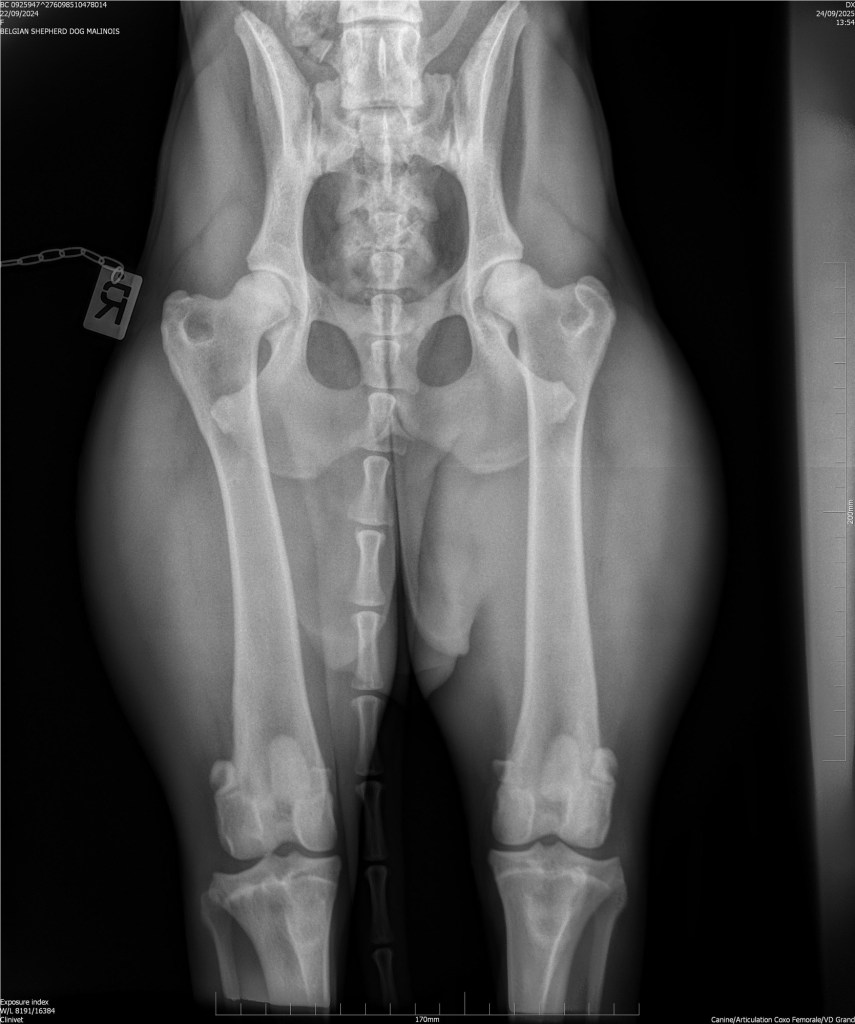

Hips 2/3